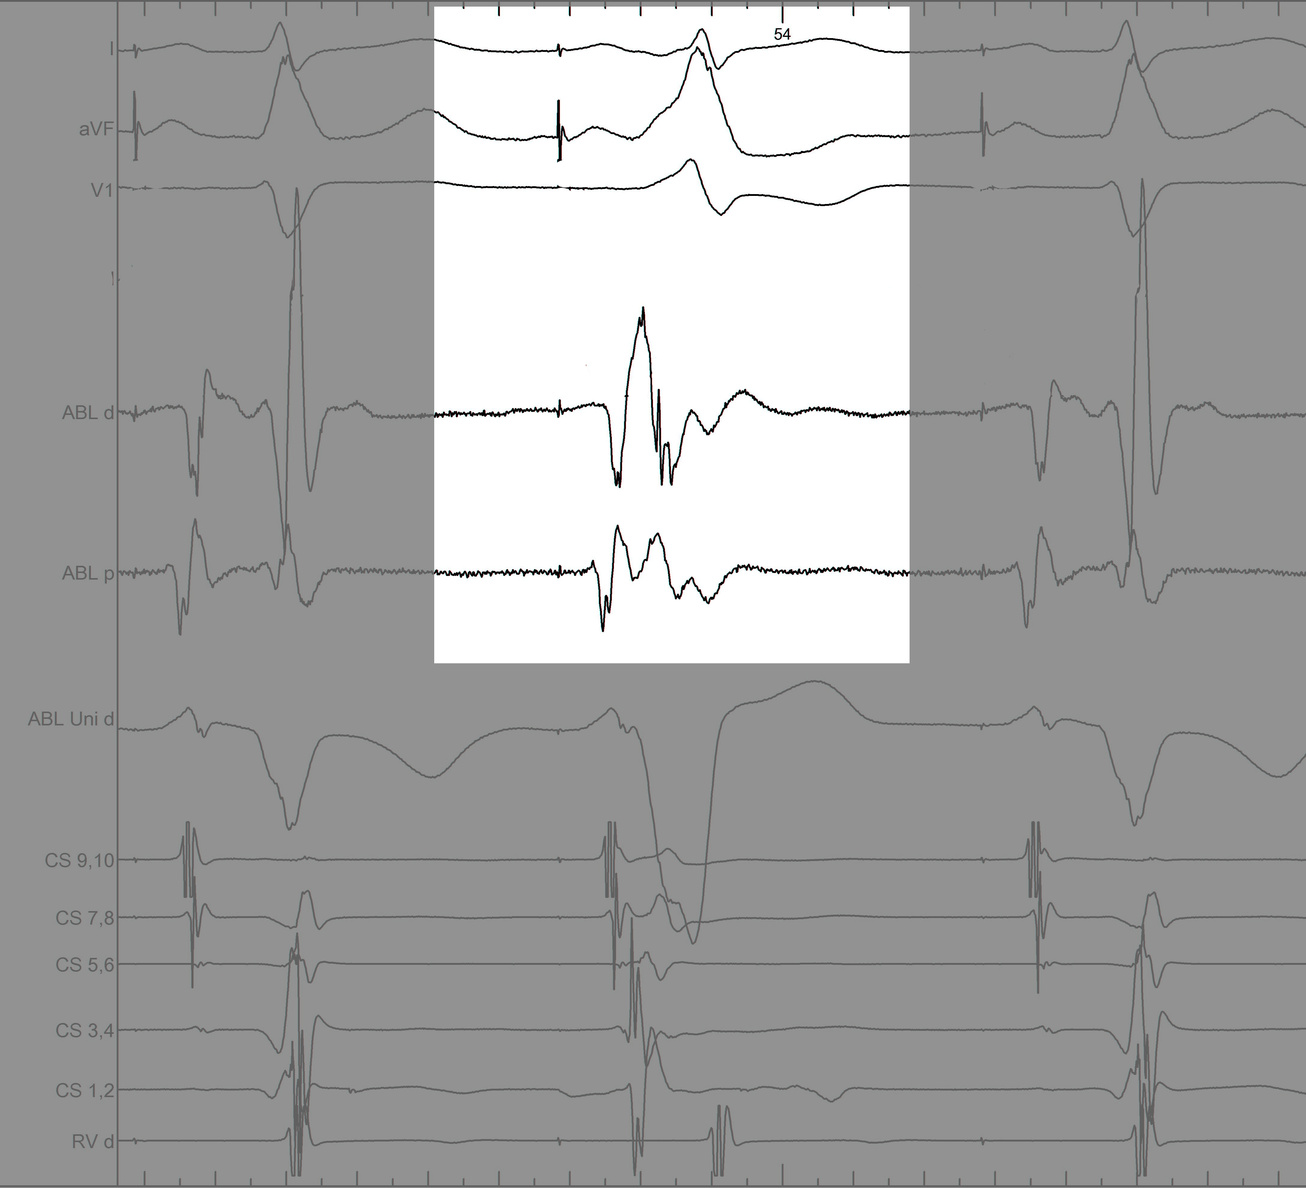

Mapping in diverticulum

signals.jpg

Mapping in diverticulum - CSE potential most important

div_schematic.jpg

Selvaraj RJ et al. Radiofrequency ablation of posteroseptal accessory pathways associated with coronary sinus diverticula. J Interv Card Electrophysiol. 2016 Nov;47(2):253-259. doi: 10.1007/s10840-016-0113-x.